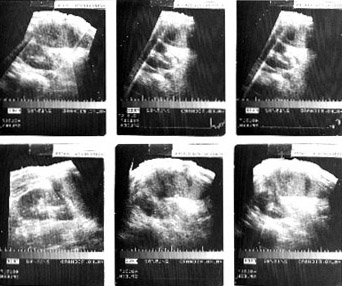

Splenic Hemorrhage

• Left pleural effusion

Patient developed acute abdominal pain following a passionate hug. Developed ruptured spleen, and then presented with hemorrhagic pleural effusion.

Follow up film and spleen ultrasound below.